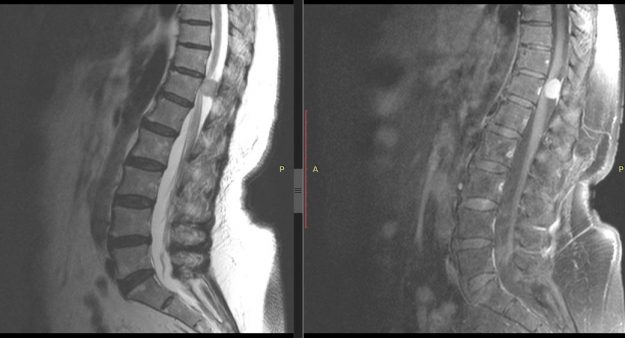

Νεαρή ασθενής 17 ετών με εκτεταμένη συριγγομυελία από την αυχενοπρομηκική συμβολή έως το τελικό τμήμα του νωτιαίου μυελού, λόγω συνδρόμου Chiari. Κλινικά αιμωδίες (μουδιάσματα) άνω άκρων, ζάλη. Αφού ο εργαστηριακός έλεγχος απέκλεισε συνοδά προβλήματα (πχ καθηλωμένο τελικό νημάτιο κ.α.) αποφασίστηκε η επέμβαση αποσυμφόρησης του οπισθίου κρανιακού βόθρου με ανάδυση των αμυγδαλών της παρεγκεφαλίδας και μηνιγγοπλαστική.…